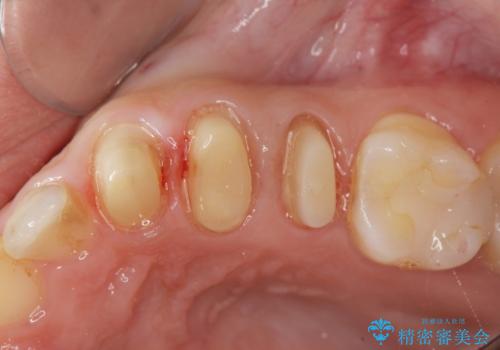

X線撮影を行い、隣接面に多発した虫歯と歯ぐきよりも深くなってしまった虫歯を小矯正をおこなったのちのセラミック治療で問題を解決します。

小矯正を行い深い虫歯を改善した後は、小手術を行うことで歯ぐき・周囲歯槽骨の状態を整えることでより安定した歯周環境を得ることができます。